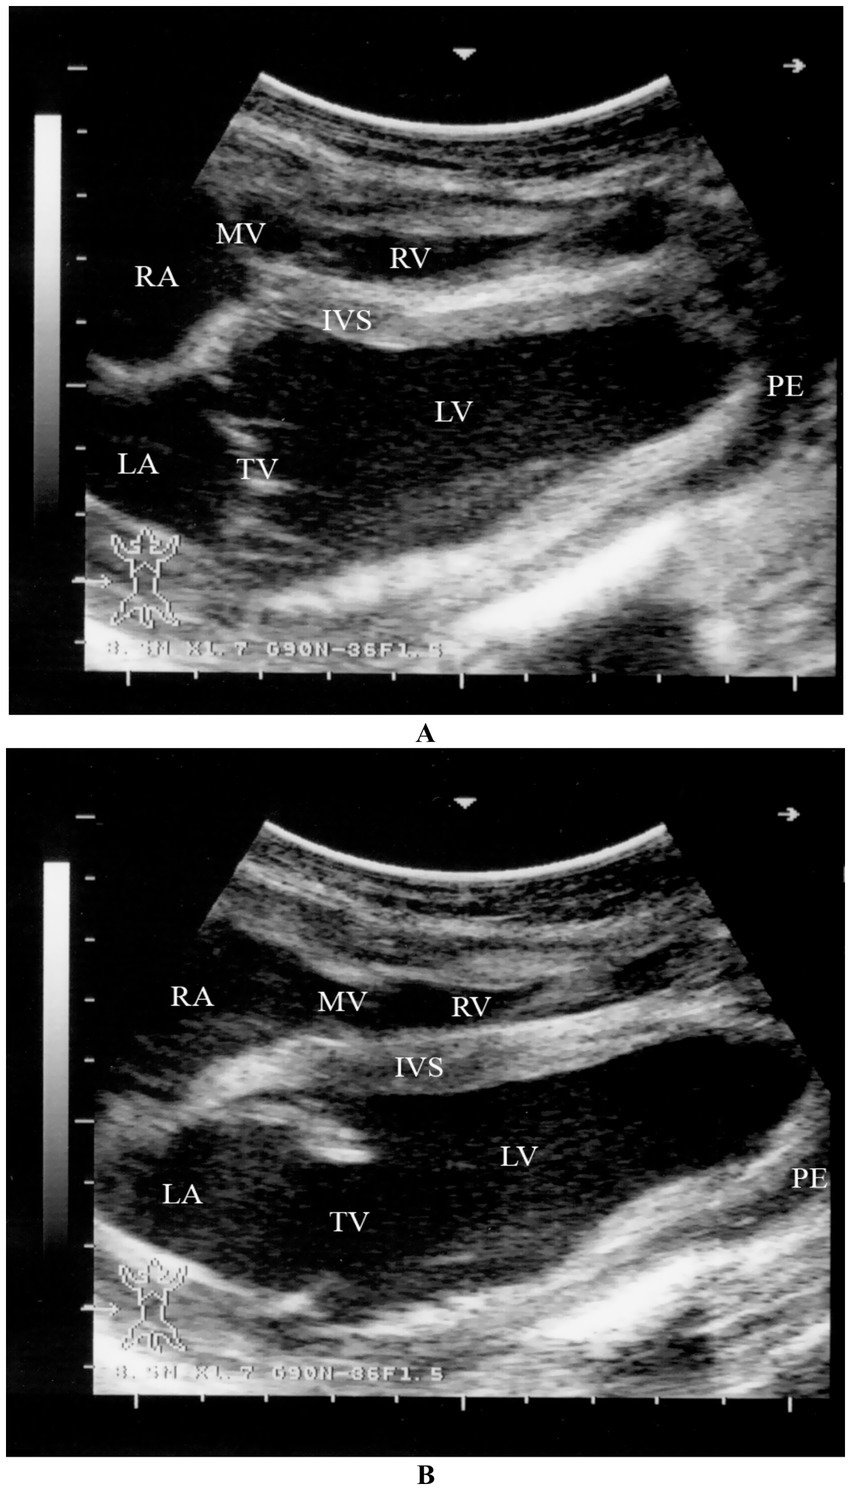

Myocardial degeneration, also known as nutritional muscular dystrophy or white muscle disease, is a metabolic disorder caused by selenium and/or vitamin E deficiency. It can lead to necrotic myocarditis with heart failure or myocardial fibrosis, reducing cardiac efficiency. The disease is commonly seen in intensively managed camels and rapidly growing camel calves. It occurs in two clinical forms: acute (cardiac) and sub-acute (musculoskeletal). The acute form of the disease primarily affects the heart muscle and is often fatal. Affected animals may collapse and die suddenly following exertion, with no prior warning signs. Clinical signs include sudden onset of dullness, tachycardia, and increased respiratory rate. Camel calves are often found in lateral recumbency and may be unable to rise to sternal recumbency, even with assistance. Ultrasonography: Shows tachycardia and increased echogenicity of the myocardium (32) (Figure 15).

Figure 15. Two-dimensional echocardiographic assessment of a dromedary camel calf diagnosed with selenium and/or vitamin E deficiency (nutritional cardiomyopathy). (A) Right parasternal long-axis view during systole and (B) diastole demonstrate altered cardiac chamber dimensions. Quantitative measurements include right ventricular (RV), left ventricular (LV), right atrial (RA), and left atrial (LA) internal diameters. The interventricular septum (IVS) appears hypokinetic, and both tricuspid (TV) and mitral (MV) valves are identified for structural and functional assessment. These echocardiographic alterations, including chamber dilation and septal motion abnormalities, support the diagnosis of myocardial dysfunction secondary to nutritional cardiomyopathy [modified from Tharwat (32)].